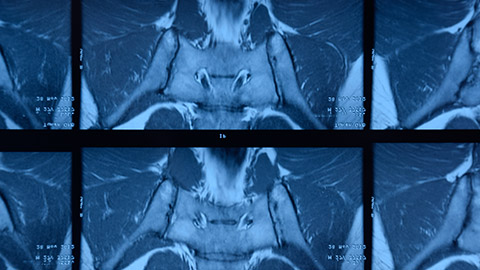

Image of Spondylitis Ankylosans

0:06:42.7 RW: There's an X-ray sign called bamboo spine that's used to describe someone who has AS, the vertebral bodies join into a single bone that looks like a fixed stalk of bamboo. I'll put a couple of Wikimedia pictures in our show notes for today to demonstrate what I mean by this. AS is a potentially dangerous disease because it can cause the spine to curve over in this really extreme flexion, it can make the ribs fused to the spine, so they don't expand and contract with breathing, that is a recipe for life-threatening pneumonia, other complications of ankylosing spondylitis range from not a big deal to really serious. Some people get irritated, itchy eyes, this is iritis during flares. Some patients get swollen hand joints and fingers, we see this with psoriatic arthritis too, and some patients, especially women have painful inflamed peripheral joints like shoulders and hips, and we heard a hint of that in our client's description. Lots of people with AS also develop osteoporosis with a high risk of spinal fractures and they may also develop heart failure because of limited space in the thoracic cavity. Ankylosing spondylitis is often, but not always linked to the presence of a particular gene called HLA-B27.

0:09:32.2 RW: There's a great name for this; Non-radiographic axial spondyloarthritis, that means damage at the spine but it doesn't show up on x-rays. The use of MRIs now show some subtler symptoms and earlier in the process, especially when they're targeted at the sacroiliac joints and not just the lumbar spine, but still ankylosing spondylitis in women is often missed in its early stages, and that means women are likely to be at a more advanced stage of the disease when they are diagnosed with a higher burden of tissue damage, a large systematic review showed that it takes women about two years longer to be correctly diagnosed with AS compared to men. Most resources say that the signs and symptoms of ankylosing spondylitis are more or less the same for men and women, especially with the experience of low back pain, which we didn't hear about in the description of our client, but that might be implied. Women are also more likely to have joint pain elsewhere like the neck or the shoulders, the most common signs and symptoms include dull pain and stiffness in the low back and SI joints, back pain that's often unilateral, and this pain tends to be worse after rest, but then it subsides with movement and exercise, some people have a low-grade fever, especially during flare, and they might experience a loss of appetite and a loss of energy. As the disease progresses, we can expect to see bilateral pain and stiffness in the neck, ribs, shoulders, hips and heels.